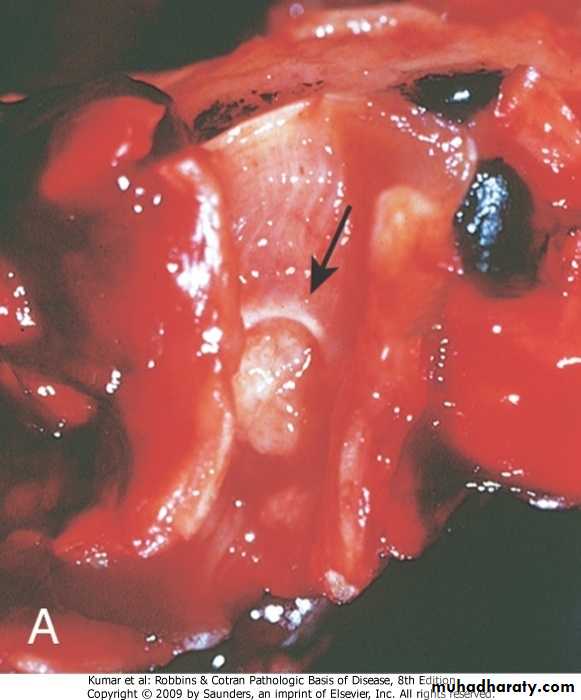

Carcinoid tumor

Low grade malignant tumor

Affect younger age group than carcinoma

Both sexes are affected equally

It form a nodule may be central or peripheral

It can metastasize

May produce vasoactive amines leading to carcinoid syndrome

Histologically consist of uniform cells

Bronchial carcinoid

Respiratory  System